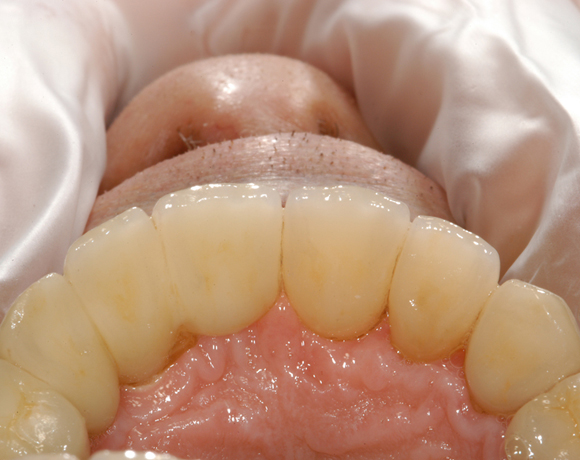

6 Implantate und viele Kronen und Brücken

Mit dem zweiteiligen vollkeramischen Implantat lassen sich auch große Lücken überbrücken.

Im vorliegenden Patientenfall waren die Zähne 11 – 26 mit einer provisorischen Brücke versorgt, der Patient konnte damit aber nicht essen. Auch im Unterkiefer waren die vorhandenen Kronen und Brücken insuffizient. Es wurde eine komplette Neuversorgung für Ober- wie Unterkiefer geplant.